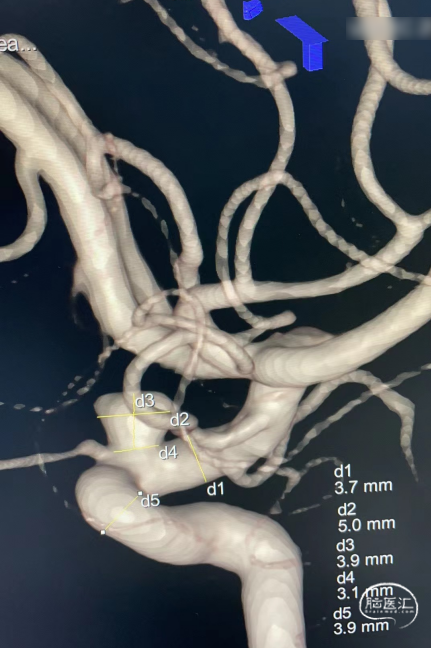

病例3

左侧颈内动脉眼动脉段动脉瘤

术前影像

诊断:左侧颈内动脉眼动脉段动脉瘤,动脉瘤瘤体直径5.0mm,瘤颈直径3.1mm,载瘤动脉远端直径3.7mm,近端直径3.9mm,密网支架将落脚于直径略大的较平直段血管处。

处理策略:使用弹簧圈1枚,1枚如意SM*FDD-450-25mm治疗。